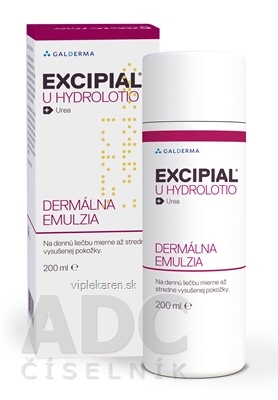

EXCIPIAL U HYDROLOTIO emu der 1×200 ml

Pôvodná cena bola: 8,90€.8,70€Aktuálna cena je: 8,70€. s DPHNa sklade